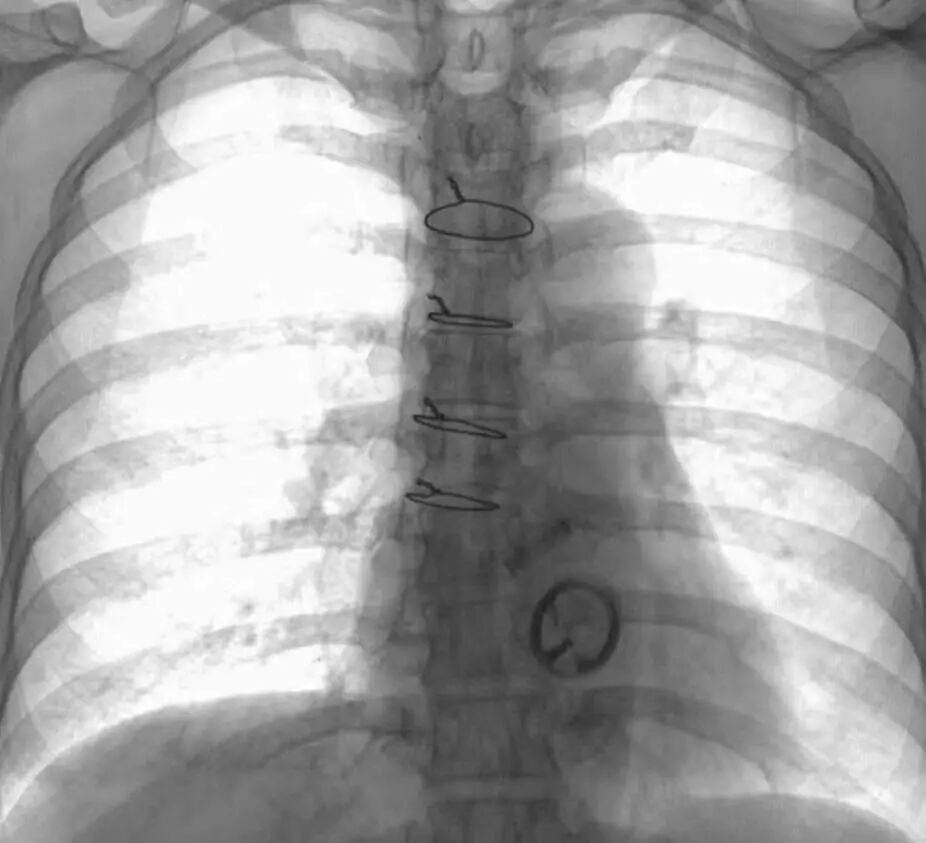

输液泵和留置导管

MRI检查:可做

输液泵通常植入于胸部皮下,由穿刺座和静脉导管系统组成,材料主要有合金、硅橡胶和塑料等,呈非铁磁性和弱磁性,因此进行MRI检查是安全的。

值得注意的是,因为强磁场可能会破坏胰岛素泵功能,因此带有胰岛素泵的患者在进入MRI检查室时应移除胰岛素泵。